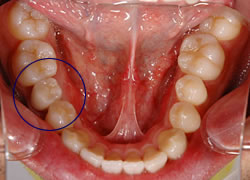

Case 2

術前